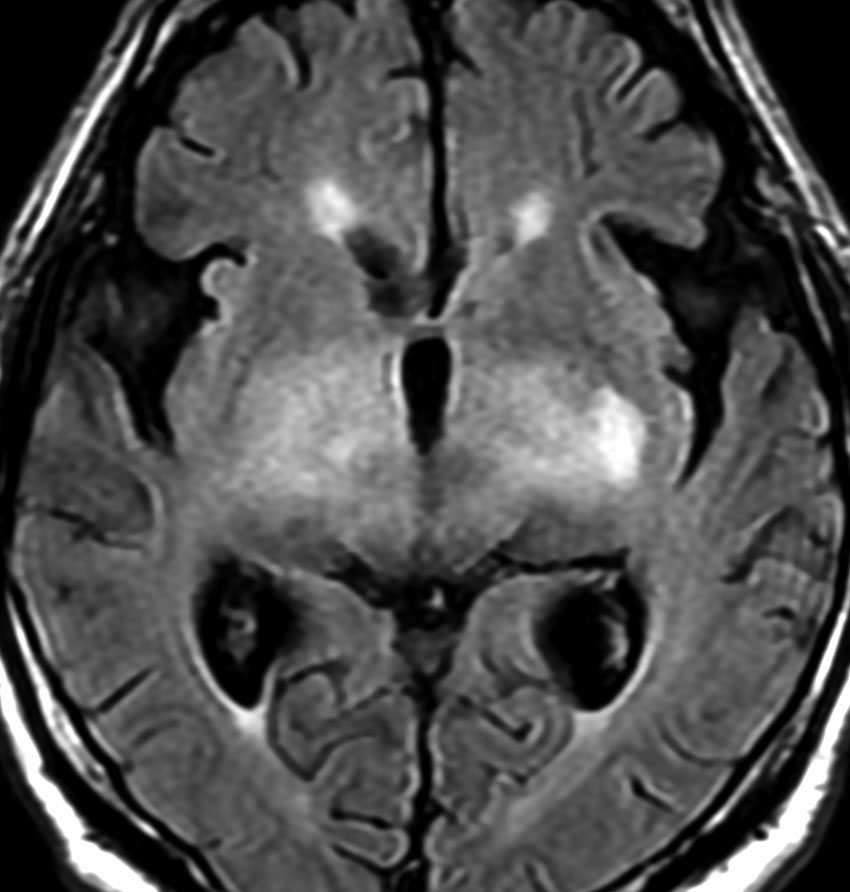

MRI画像所見 60代で嚥下障害と構音障害で発症した例

延髄から中脳まで腫瘍があって脳幹部が腫れています。この画像ですと,小児のびまん性橋膠腫(DIPG,びまん性正中グリオーマ)のように見えます

両側視床から大脳基底核,両側大脳半球深部白質,脳梁まで広範囲に腫瘍が存在します。退形成性星細胞腫のようにまだらにガドリニウム増強されます。